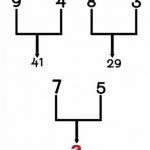

Najjednostavnija podjela karcinoma pluća, koju svi trebamo znati, je slijedeća:

– mikrocelularni karcinom pluća (eng. small cell lung cancer SCLC) i

– nemikrocelularni karcinom pluća (eng. non-small cell lung cancer).